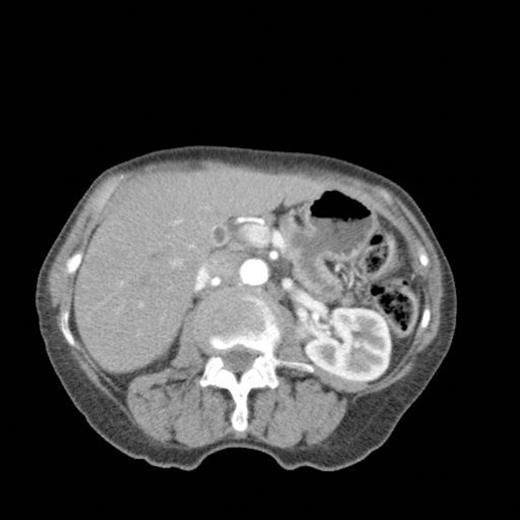

CT scan showing marked dilatation and tortuosity of the main pancreatic duct (12-13mm at the head) with atrophy of the body and tail

CT scan done 2 years later revealed marked dilatation and tortuosity of the main pancreatic duct (12-13mm at the head) with atrophy of the body and tail (Fig1). Repeat scans done on an yearly basis over the next three years reported no progressive change. CT scan done 6 years after the original diagnosis revealed pancreatic duct dilatation to 15 mm with side branch dilatation in uncinate process and atrophic pancreas (Fig 2). A diagnosis of mucinous ductal ectasia or an intraductal papillary mucinous tumour was suggested. On clinical review, patient complained of epigastric discomfort, loose stools, anorexia and weight loss. Upper GI endoscopy and colonoscopy was normal. Faecal elastase was less than 100 confirming pancreatic insufficiency for which she was commenced on creon.